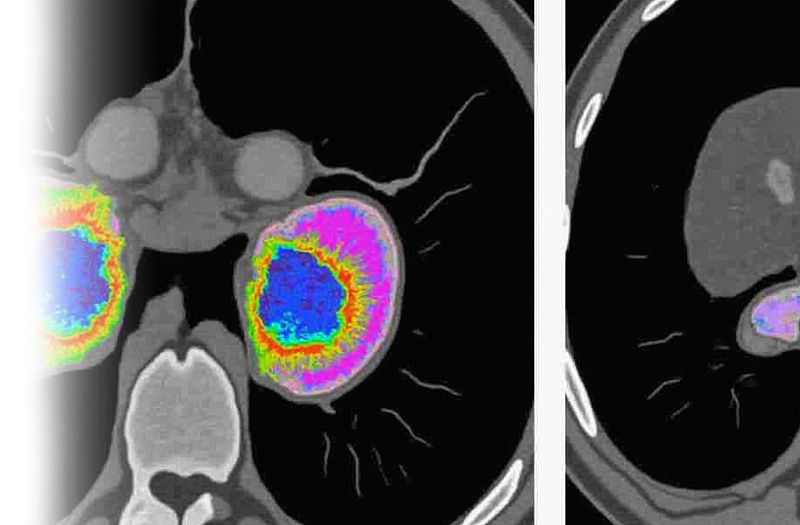

Компьютерная томография почек и надпочечников – важный метод прицельного исследования состояния почек и надпочечников.

Показания для проведения КТ почек и надпочечников:

• гиперплазия;

• узловые образования надпочечников;

• конкременты в полостной системе почек.